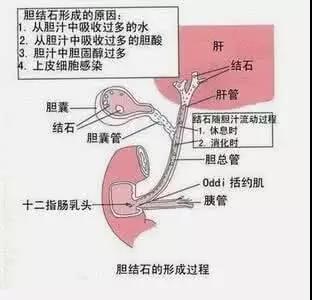

追问病史,说有右肩胛区隐痛2年余,但因为症状不明显,拍拍揉揉就好了,也就没有当一回事,去年10月医院常规体检时做过一个腹部CT,发现胆囊颈有一个3mm大小的结石,但也没有引起重视。发病前天晚上在跑步机上跑了一个小时,第二天早晨也是爬楼梯来上班的。

据当时参与抢救的结石科主任介绍,我们这位同事发生急性胰腺炎的罪魁祸首就是那颗小结石,是典型的胆源性胰腺炎。由于结石从胆囊掉出,嵌顿在壶腹部,使胆道内压力剧烈增高,高压的胆汁逆流胰管,造成胰腺腺泡破裂,胰酶进入胰腺间质而发生胰腺炎。如果处理不及时,可发展为重症胰腺炎,死亡率很高。万幸的是该同事的结石自己掉出来了。